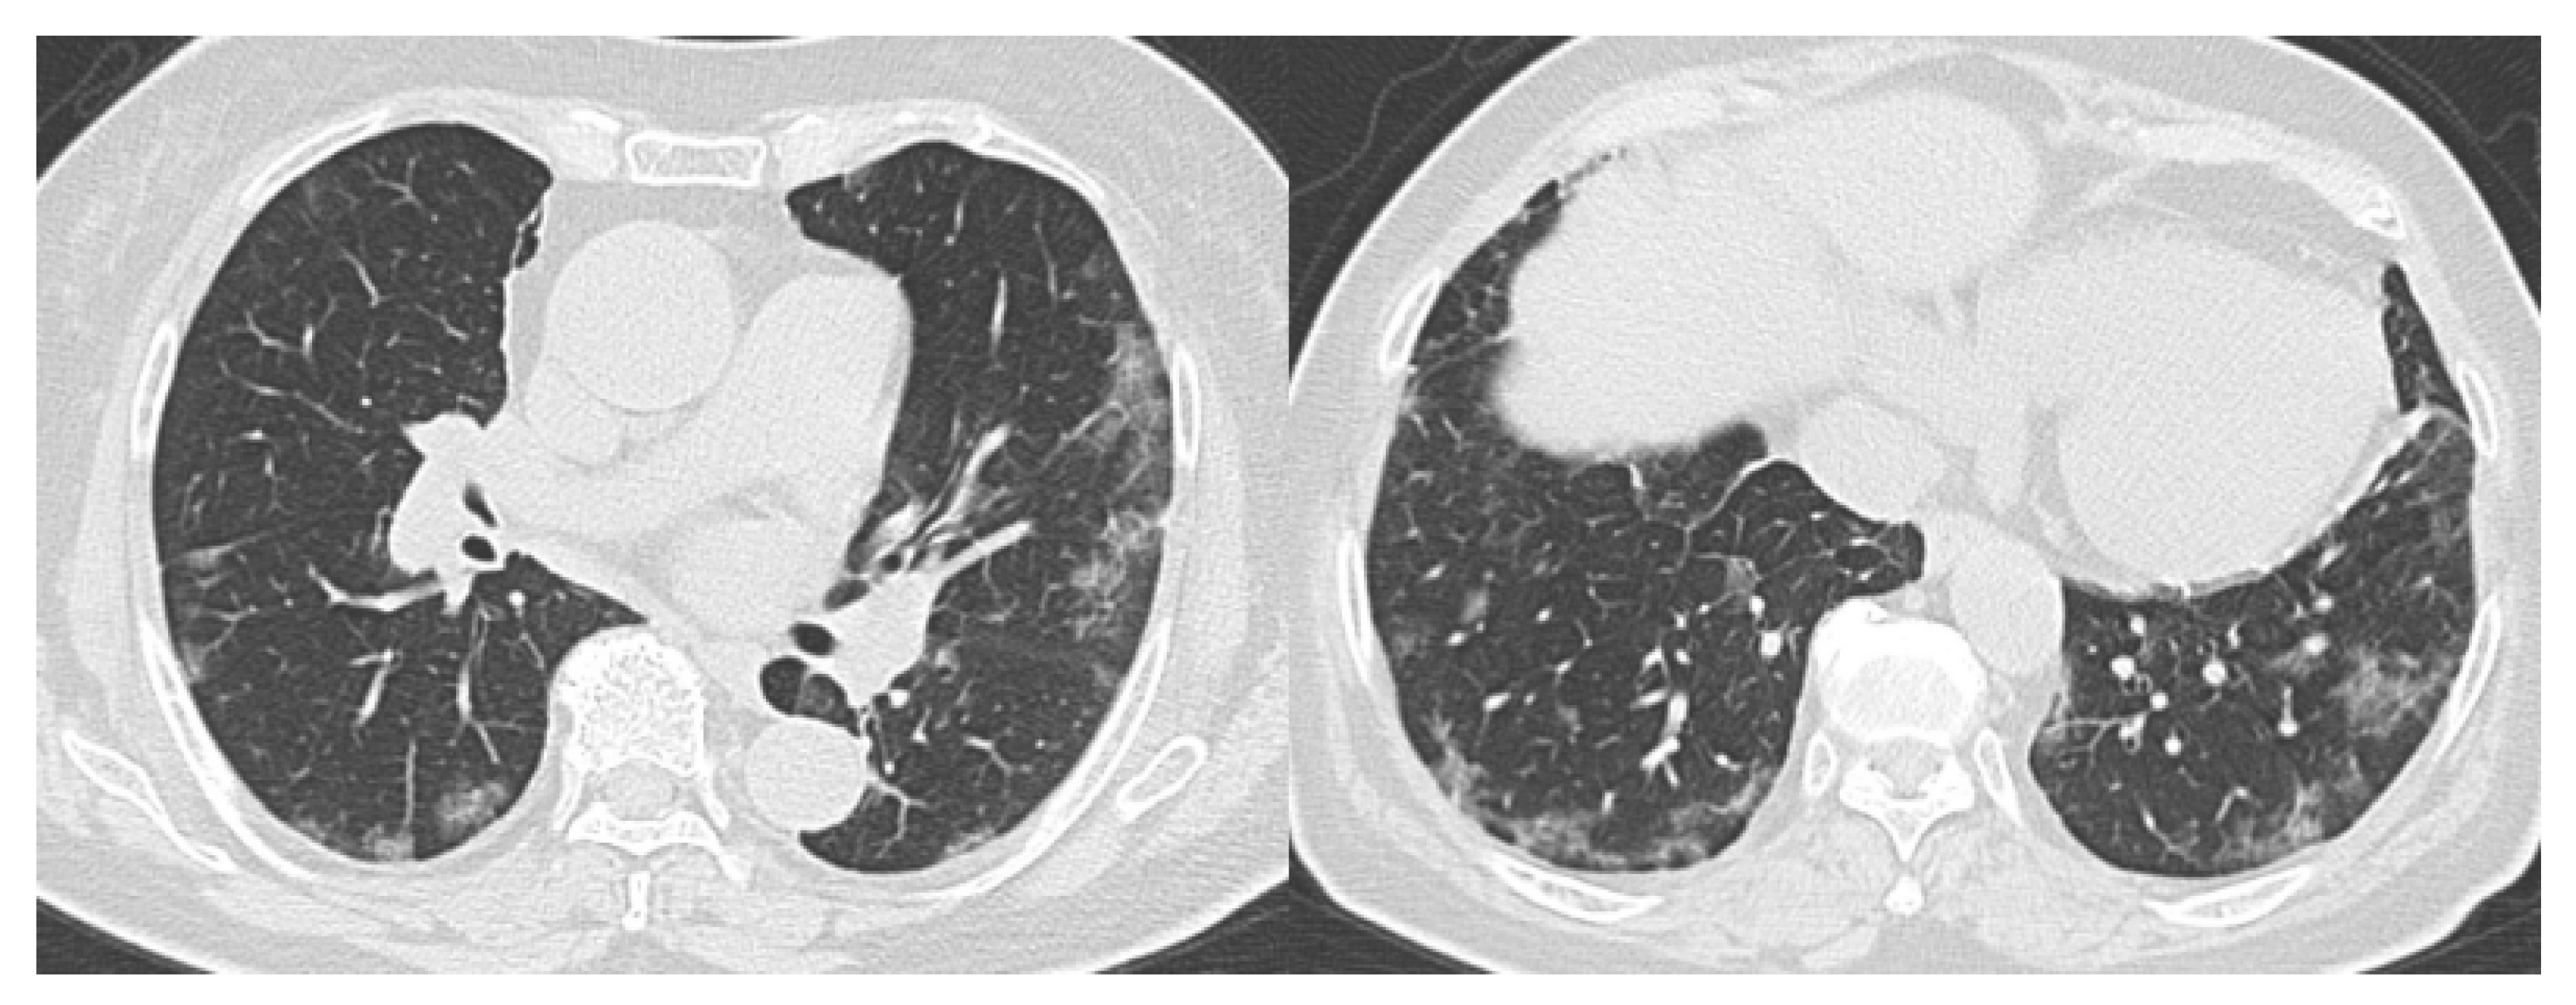

- CO-RADS 2 means a low level of suspicion for pulmonary lesion resulting from COVID-19, based on CT findings in the lungs typical of etiology indicative of infections other than COVID-19, including bronchitis, infectious bronchiolitis, bronchopneumonia, lobar pneumonia, and pulmonary abscess. Findings include a tree-in-bud sign, a centrilobular nodular pattern, lobar or segmental consolidation, and lung cavitation.

- CO-RADS 3 means CT findings equivocal for pulmonary involvement of COVID-19 that can also be seen in other types of viral pneumonia or non-infectious etiologies. Findings include perihilar ground-glass, homogenous extensive ground-glass with or without sparing of some secondary pulmonary lobules, or ground-glass together with smooth interlobular septal thickening with or without pleural effusion in the absence of other typical CT findings.

- CO-RADS 4 means a high level of suspicion for pulmonary lesion resulting from COVID-19, based on typical CT findings but exhibiting some overlap with other types of (viral) pneumonia. Findings are not located in contact with the visceral pleura or are located strictly unilaterally, have a predominantly peribronchial distribution, or overlap with severe diffuse preexisting pulmonary abnormalities.

- CO-RADS 5 means a very high level of suspicion for pulmonary lesion resulting from COVID-19, based on typical CT findings. Obligatory features are ground-glass opacities, with or without consolidations, close to visceral pleural surfaces, including the fissures, and a multifocal bilateral distribution.